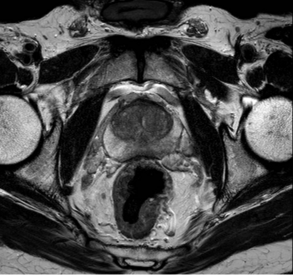

最近,前列腺癌在診斷方面取得了很多進展。對於 PSA 升高的男士,可以安排磁力共振掃描(MRI)來評估前列腺內有沒有任何腫瘤或陰影。 MRI圖像也可以融合到用於前列腺活檢的超聲波圖像中,讓醫生可以在懷疑有前列腺腫瘤的地方進行針對性活檢。這樣能提高前列腺活檢的準確度。另一方面,如果 MRI 掃描顯示前列腺器官完全正常的話,也有可能安全地避免前列腺活檢的需要。